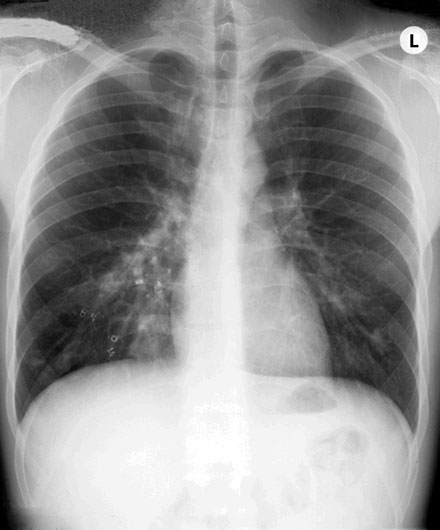

Trouble in the chest, in a lady with a stroke. Surely you can just see the outline of the oval density in the right base through the liver!

The cause of the stroke in this lady is most likely the arteriovenous malformation in the posterior parietal region, where multiple ectatic sections are present which drain into superior sagittal sinus. Thrombus may form in the dilations and lead to a stroke or they could be areas of haemorrhage. However, in this case, the arteriovenous malformations in the lungs could also have been the source of an embolus.

Lady with transient ischaemic attacks. Note the rounded density lateral to the right breast.

Which in the lateral projection can be clearly seen projected over the heart.

This turned out to be another AV malformation which was occluded by multiple coils. Note the post embolisation picture in the bottom right corner.

This 18 year boy had an abnormally high haemoglobin and tired easily. There were small blue venous spiders around his lips. Note the variety of rounded densities in both lungs.